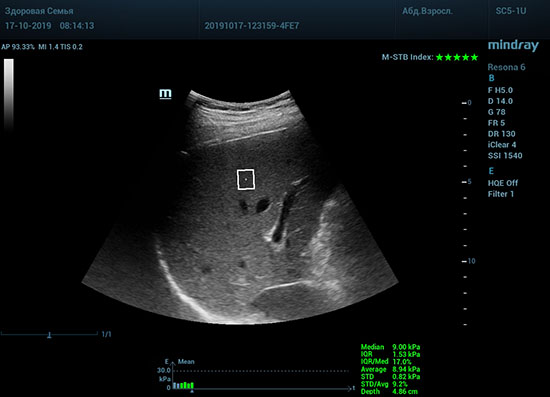

Датчик посылает ультразвуковую волну способную сжать участок паренхимы печени. В момент расправления тканей органа после сжатия, происходит образование поперечные волн. Для их регистрации, следом за волной сжатия, посылается регистрирующая волна, которая улавливает изменения скорости. Закономерность изменения скорости позволяет использовать модуль Юнга для оценки плотности ткани. Таким образом мы получаем аналог FibroScana’а, который упоминается в рекомендациях по диагностике и лечению жировой болезни печени, фиброза и цирроза. Разница в том, что теперь не нужно приобретать отдельный прибор. Все уже есть в ультразвуковой системе. Быстрее, дешевле, доступнее. Так же исчез пугающий пациента эффект «удара» типичный для фиброскана. Методика, в отличии от биопсии, не инвазивная и может применяться даже у детей.

Определение плотности печени. Не ошибся ли оператор при измерении эластических свойств печени? Для оценки критериев качества предусмотрен индекс MBT, который покажет насколько «твердой» была рука оператора и двигалась ли печень. При MBT 5* рука тверда и показатели достоверны. Для оценки качества результатов используется IQR индекс, отображающий колебания показателей в точке измерения при расчете медианы. Показатели при IQR <30% считаются приемлемыми. Техника сканирования через межреберные промежутки требует размещение окна интереса на несколько сантиметром ниже капсулы, для исключения эффекта реверберации. Установка ROI на паренхиму без захвата сосудов, для исключения погрешностей измерения.